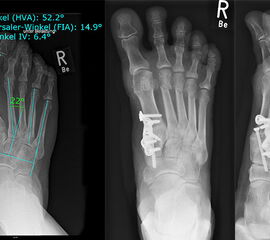

In unserer prospektiven Studie wurden 10 Patienten (8 Frauen und 2 Männer; Ø Alter 58 ¼ Jahre) mit einem symptomatischen Hallux valgus bei Pes adductus und Metatarsalgie mittels einer Lapidusarthrodese und einer lateralisierenden DMMO versorgt. Die Fusion des TMT-I-Gelenkes erfolgte offen mittels einer winkelstabilen, plantaren Platte. Alle zusätzlichen distalen Eingriffe (DMMO, Isham-OT, Akin-OT, Kleinzehenkorrekturen) wurden in minimalinvasiver Technik durchgeführt. Die Patienten wurden nach 6 Monaten klinisch und radiologisch nachuntersucht.

Der präoperative AOFAS-Score betrug 41,5 Punkte und konnte postoperativ auf durchschnittlich 86,2 Punkte verbessert werden (p<0,005). Der IMW reduzierte sich von Ø 16,7° (8,5°-20,3°) präoperativ auf Ø 7,14° (6,1°-9,5°) (p<0,005). Ebenso konnte der HVW von präoperativ Ø 45,2° auf postoperativ Ø 9,4° (p<0,005) korrigiert werden. Durch die Durchführung der modifizierten, lateralisierenden DMMO veränderte sich der präoperative VAW von Ø 23° (19,3°-33,5°) auf Ø 15,6° (13°-17,2°; p<0,004).

Bei einem Patienten wurde eine verzögerte Wundheilung im Bereich der Lapidusarthrodese beobachtet, die jedoch keine operative Revision erforderte. Pseudarthrosen des TMT 1-Gelenkes wurden nicht beobachtet. Ebenso kam es in allen Fällen zur vollständigen Konsolidierung der DMMOs, wobei einige Patienten über eine mehrere Monate anhaltende Schwellneigung berichteten. Dies ist ein bekanntes postoperatives Merkmal der DMMO 25 und wurde von allen Patienten bei entsprechender präoperativer Aufklärung akzeptiert und gut toleriert.